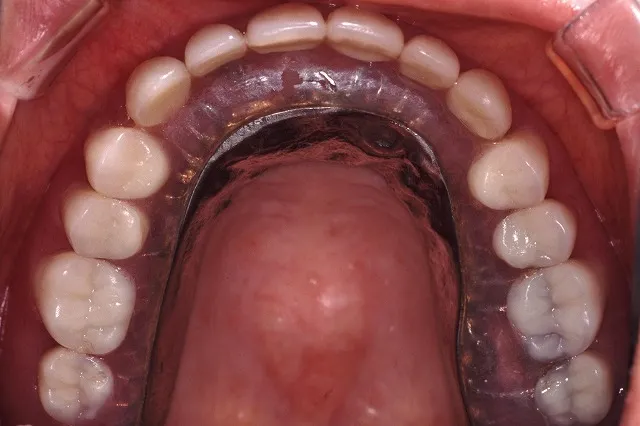

■治療後